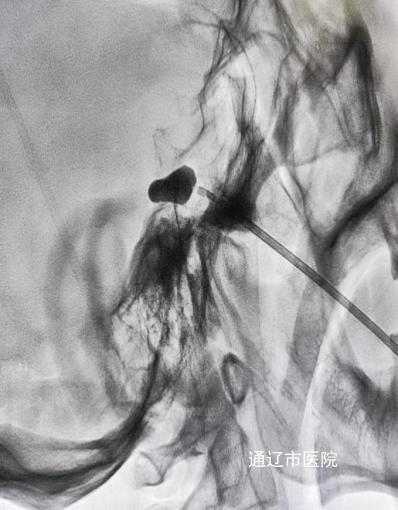

乌日勒格经过详细问诊及评估检查后,考虑到她的疾病及身体综合状况,决定采用半月神经节阻滞麻醉下三叉神经微球囊压迫术治疗。手术由乌日勒格、翟志超在介入手术室医护的配合下于患者面部穿刺,在X线引导下经卵圆孔将球囊导管置入麦克氏腔,注射造影剂扩张球囊,待球囊扩张呈“梨形”后,精准压迫引起疼痛的半月神经节2分钟,完成后拔出穿刺针及球囊导管,手术成功,赵大妈多年困扰的疼痛感立即消失,露出了久违的笑容。